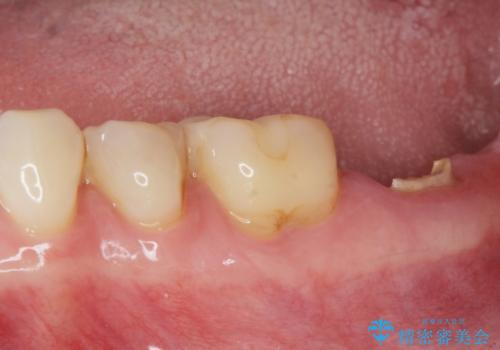

- 「歯から異臭がする。」とのことで相談に来院されました。

X線検査を行ったところ、セラミッククラウン下に虫歯が再発し、歯の破折も認めました。

歯の抜去を行い、骨の造成を含めたインプラントによる咬合機能の回復を図ります。